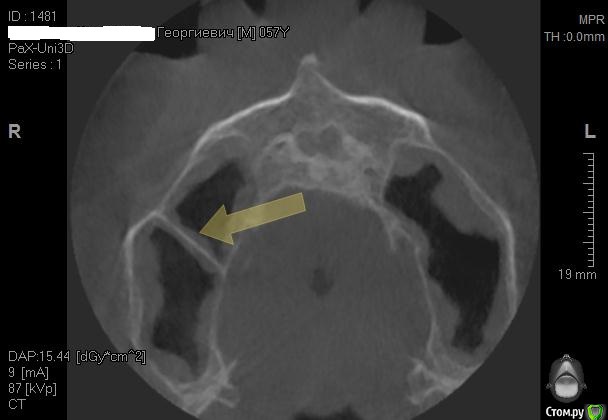

Alexey Doc Опубликовано 28 апреля, 2015 Поделиться Опубликовано 28 апреля, 2015 При просмотре КТ еще обращаю внимание на состояние решетчатых воронок, зачастую при их окклюзии есть проблемы в пазухах.на картинке цифрой 3 обозначена. Если патологии не видите то по тактике согласен, если есть вопросы то консультация Лора 1 Ссылка на комментарий

Alexey Doc Опубликовано 26 апреля, 2015 Поделиться Опубликовано 26 апреля, 2015 Можете показать срез, где видны решетчатые воронки?Почему то не получается загрузить картинку с планшета для примера Ссылка на комментарий

Kostoprav Опубликовано 26 апреля, 2015 Автор Поделиться Опубликовано 26 апреля, 2015 Можете показать срез, где видны решетчатые воронки?Почему то не получается загрузить картинку с планшета для примеравы имеете в виду в аксиальной проекции ? Ссылка на комментарий